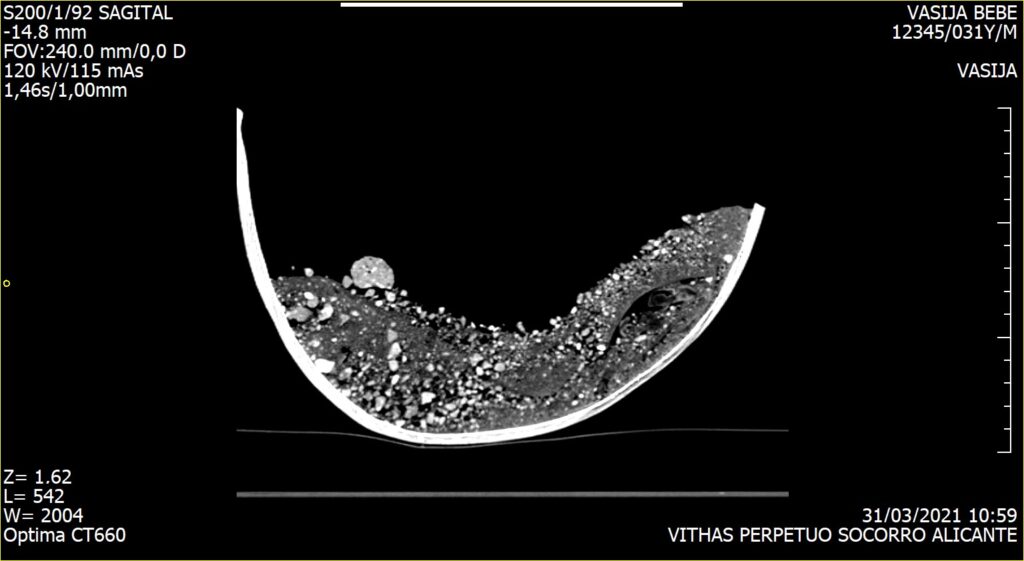

Debido a la fragilidad de los huesos se planteó la posibilidad de realizar un estudio radiológico que permitiría obtener la imagen del interior de la olla sin necesidad de ser excavada.

Este estudio, pionero en este tipo de enterramientos, fue realizado por el Hospital Vithas Alicante, quien puso a disposición de los arqueólogos, los mejores profesionales y los medios técnicos más avanzados para la consecución con éxito de esta tomografía computarizada aplicada a la Arqueología. Las pruebas practicadas revelaron que el cuerpo del perinatal se adaptaba a las paredes de la olla y que el cráneo se encontraba fracturado, quedando ambas partes solapadas.